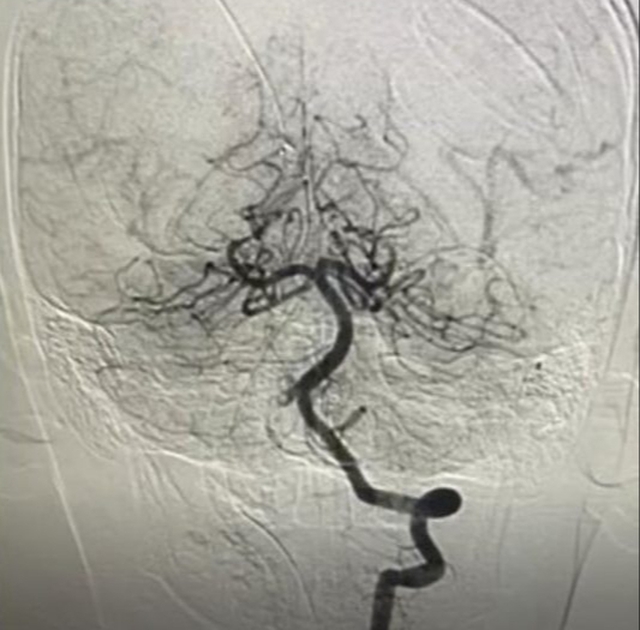

Hình ảnh chụp mạch máu xóa nền DSA. Ảnh: BVCC

Ngay lập tức, bệnh viện tổ chức hội chẩn liên chuyên khoa, thống nhất chỉ định chụp mạch não DSA để đánh giá chính xác mức độ tắc mạch và lên phương án can thiệp tối ưu.